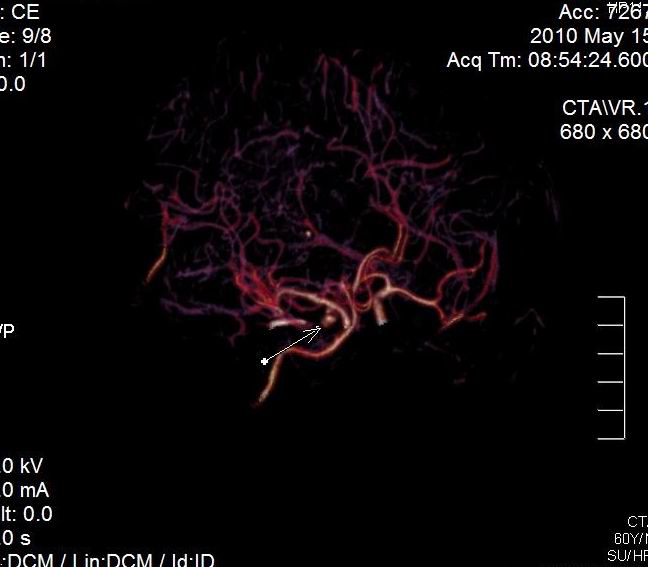

男.60岁,渐进性意识不清,ct检查双侧额颞顶部硬膜下血肿,开颅术后行脑血管cta,大脑中动脉起始部见一瘤状血管扩张。请各位老师留下宝贵意见

太常见了,报动脉瘤就可以

符合动脉瘤表现。

动脉瘤。

颅内动脉瘤。

后重建做得不是很好看,要将维蒂斯环充分显示,最好在增加一个mip。这样不好定位。

小动脉瘤

典型

符合动脉瘤的表现

动脉瘤

符合动脉瘤表现。

小动脉瘤

典型